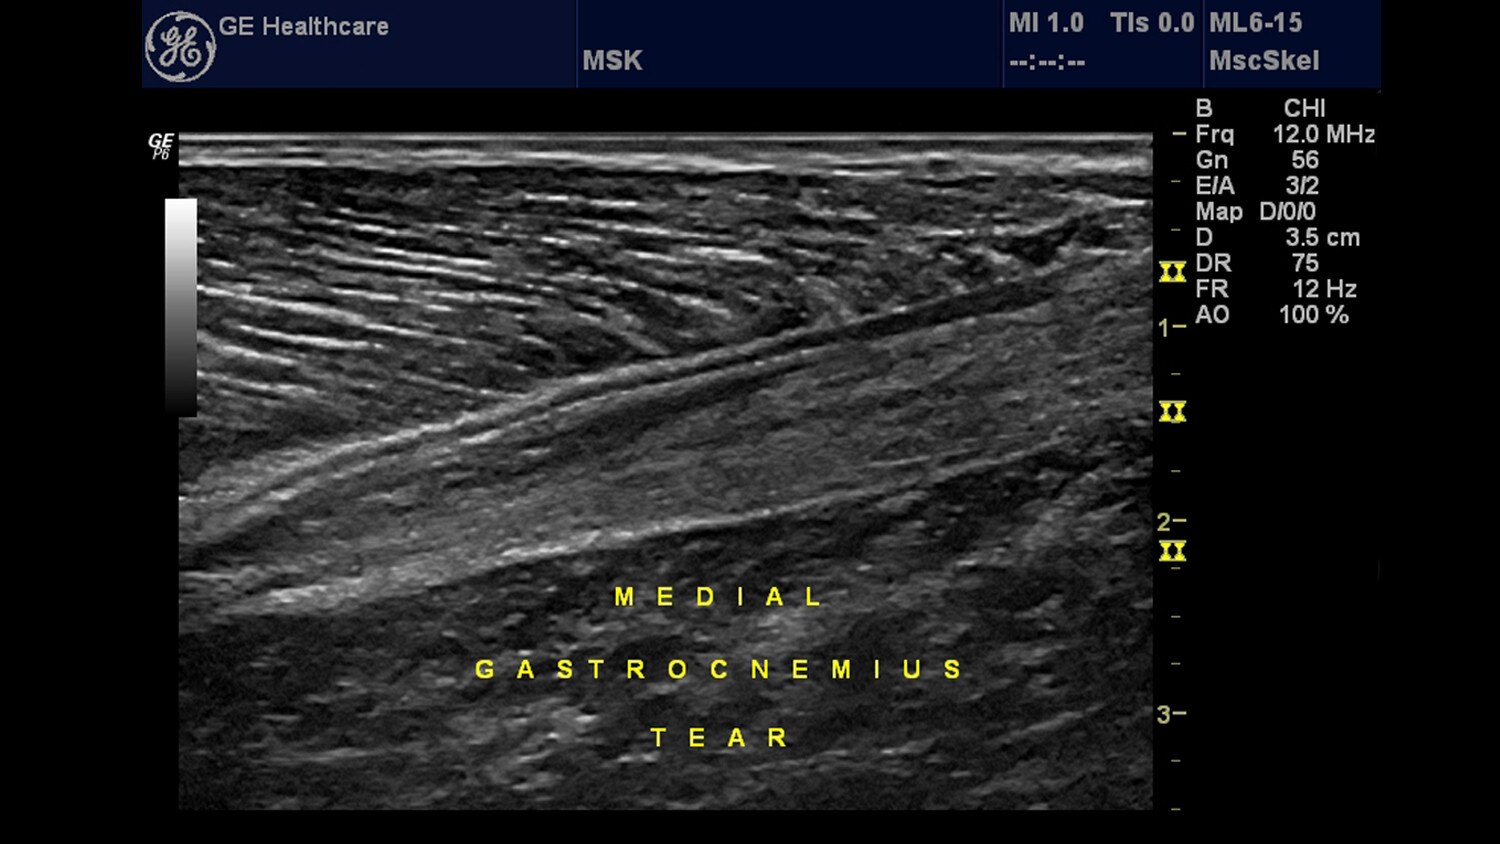

Musculoskeletal (MSK)

We are pleased to welcome you to GE's dedicated website for musculoskeletal (MSK) ultrasound!

We want to make it simple for you to access clinically relevant information that can help you successfully incorporate ultrasound into your practice or continue your search for topics to help advance your knowledge. This is a site designed specifically for you, the musculoskeletal specialist, to provide one-stop access to ultrasound information.